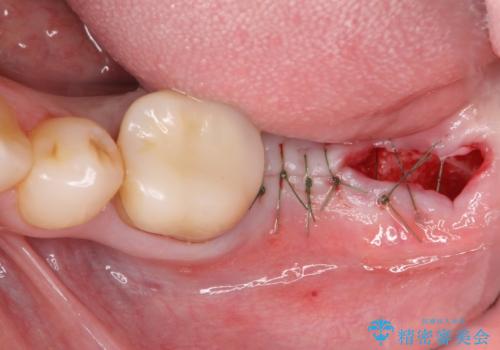

最後方臼歯の治療について

最後方臼歯を喪失した場合、入れ歯・インプラントによる咬合機能回復方法があります。

今回はしっかりと噛むことができ、取り外しの必要のないインプラントによる補綴を行いました。